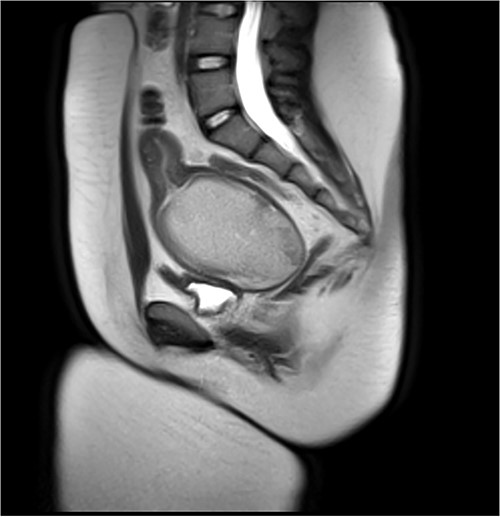

She remained suppressed and without pain. She discontinued the norethindrone acetate 2 months prior to surgery to allow re-accumulation of the HMC. The surgical team was prepared to perform a buccal graft vaginoplasty, but sufficient mobilization of the native vaginal tissue allowed for an uncomplicated vaginoplasty without graft. A uterine tamponade balloon was placed and expanded with 180 ml of sterile water. Postoperatively she was admitted with a uterine tamponade balloon and urinary catheter in place. These were removed on postoperative Day 5, and she was discharged home on doxycycline and metronidazole for a 7-14 day course and 25 mm stent at night for 14 days. Subsequent vaginoscopy revealed a normal upper vagina and well-healing suture line, able to accommodate a 25 mm rectal dilator (Fig. 3). At the time of writing, she is 5 months postoperative and using the stent a few times a month.